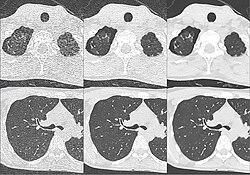

-

Craniale Computertomographie Abgebildet sind Felsenbein und Nasennebenhöhlen. Aufgrund der hohen Auflösung der Aufnahme des verwendeten 64-Zeilen-CTs sind selbst die Gehörknöchelchen erkennbar. -

Kombination aus multiplanarer Reformatierung und sliding thin slab. Der Bildkursor befindet sich im rechten Lungenflügel. Die sts-Bildstapel werden in Form von MIP-Darstellungen gezeigt (STS-MIP).[52] Links oben befindet sich eine VR-Darstellung der Lunge; sie zeigt einen Blick auf die koronal an Kursorposition geschnittene Lunge. -